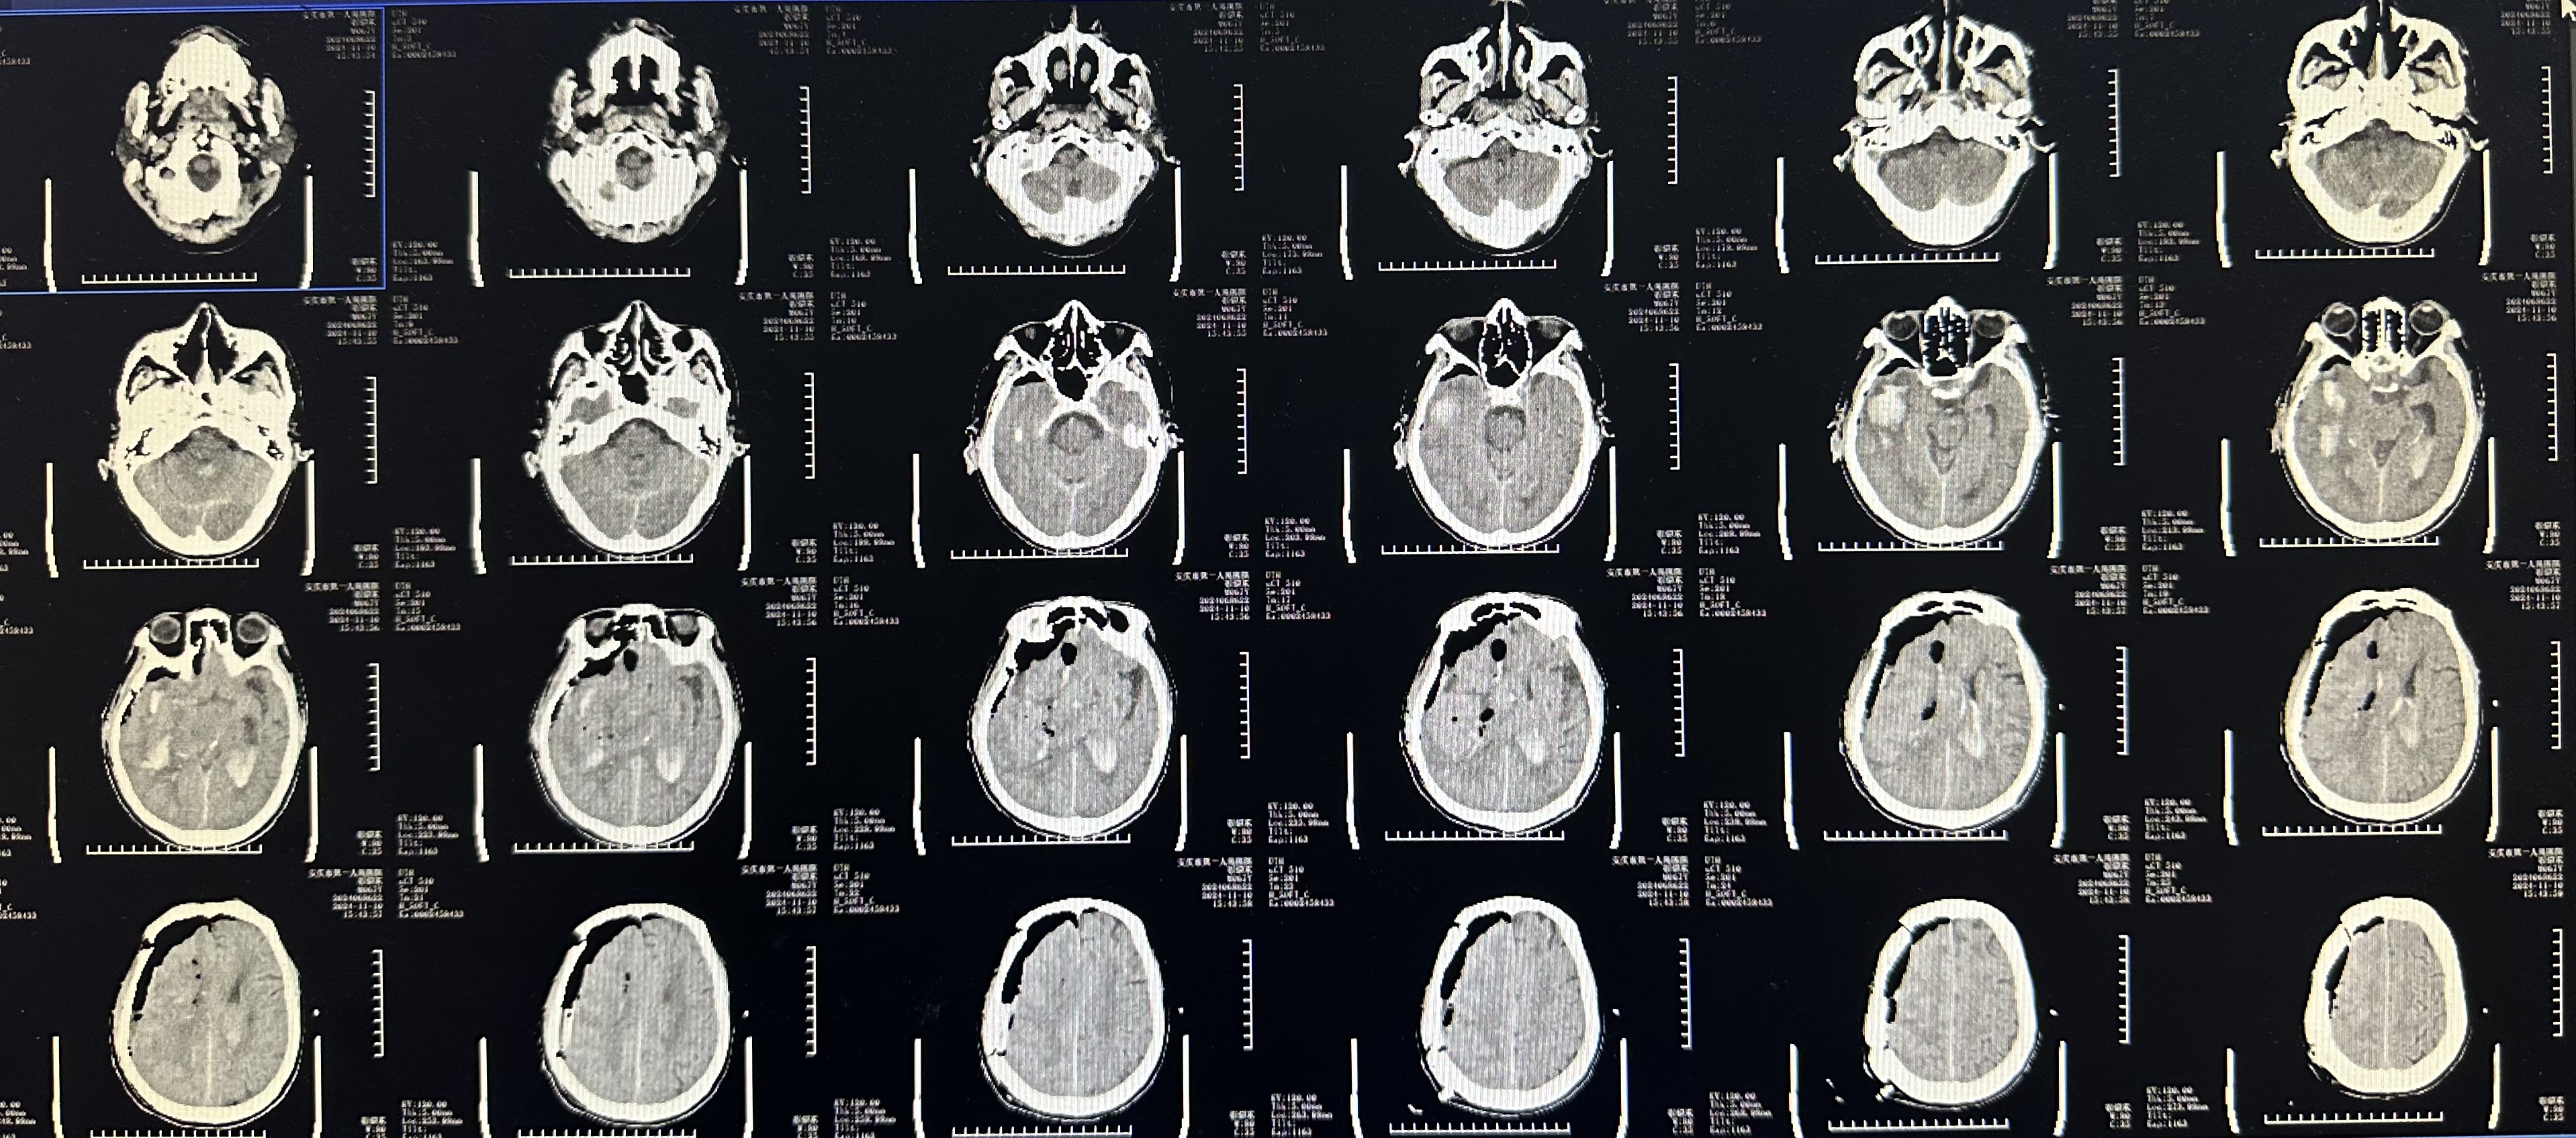

术后颅脑CT